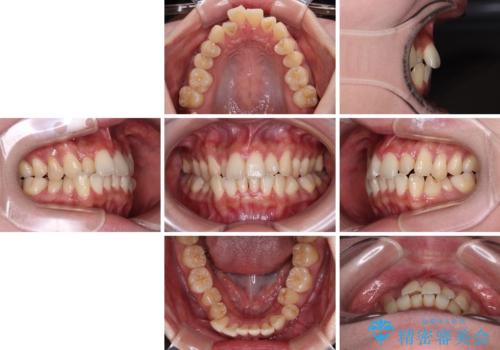

急速拡大装置 狭い歯列を拡大してクロスバイトを短期間矯正治療

- 1年4ヶ月

- 10-30回

- 上下前歯のデコボコやクロスバイトを気にして来院された患者様です。

上顎歯列が下顎の歯列に対して狭小であり、一部下顎の奥歯が上顎よりも外側に位置している状態でした。

上顎の急速拡大装置を使用して上顎骨を側方に拡大することで上顎歯列を拡大し、下顎歯列も拡大できるようにすることで、歯列を整えることとしました。

- 90万円(税込)費用は治療当時の料金となります